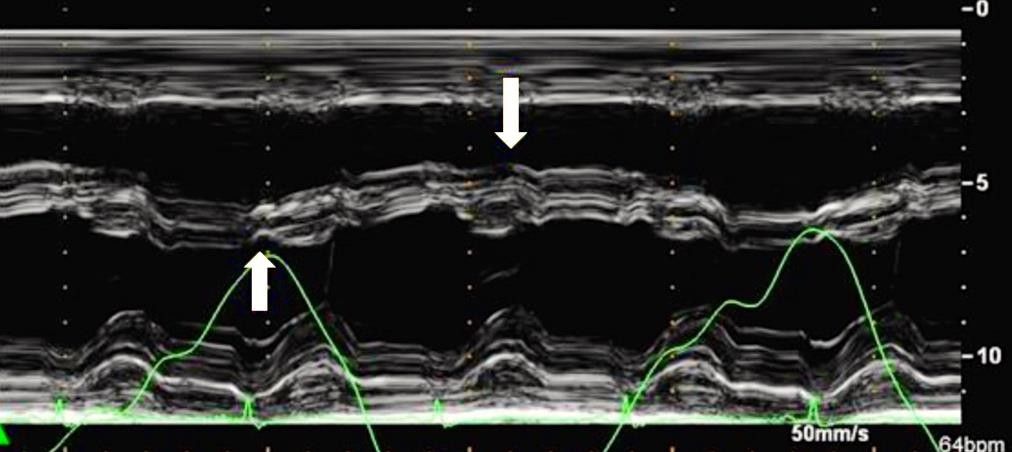

При проведении ЭхоКГ могут быть выявлены ранние признаки констриктивного перикардита, такие как парадоксальное диастолическое движение межжелудочковой перегородки (МЖП) (Приложение А3, рис. 2) [83].

Парадоксальное движение межжелудочковой перегородки во время ранней диастолы является характерным для пациентов с констриктивным перикардитом. Во время вдоха движение происходит в сторону левого желудочка, во время выдоха — в противоположном направлении [3]. При М-модальном исследовании это проявляется выемкой в раннюю диастолу при определении движения межжелудочковой перегородки, что напоминает нарушения сокращения-расслабления миокарда, наблюдаемые при блокаде левой ножки пучка Гиса или электростимуляции правого желудочка (Приложение А3, рис. 5). При определении этого признака двухмерной ЭхоКГ чувствительность составляет 62%, а специфичность — 93% [3]. Использование допплеровской визуализации тканей можно существенно увеличить чувствительность метода до 82,5% [122].